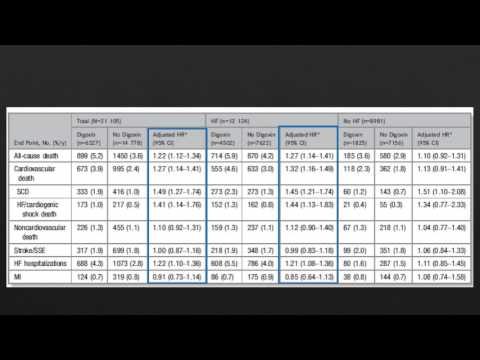

Digoxina y resultados clínicos en pacientes con FA con o sin IC. Residencia de Cardiología. Hospital C. Argerich. Buenos Aires